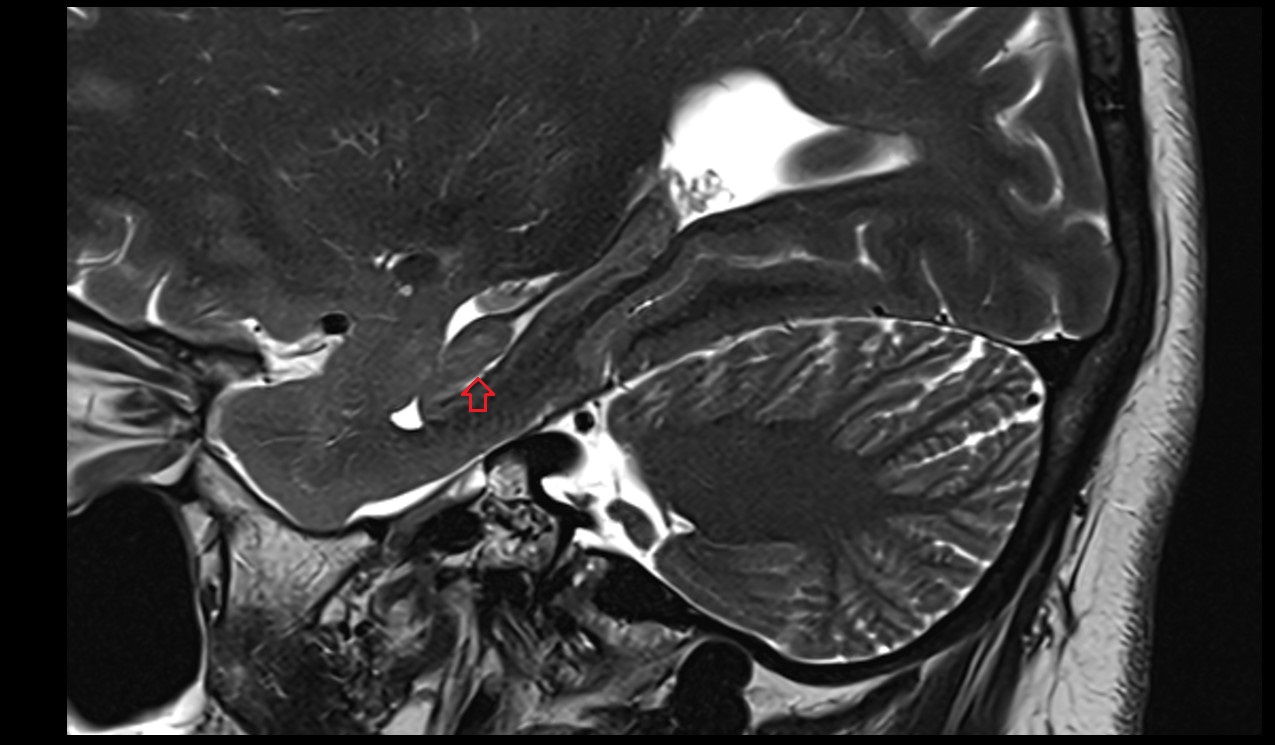

- Fetal brain

- Fetal cerebellum

- Fetal fourth ventricle

- Fetal lateral ventricle